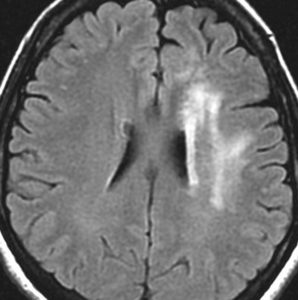

5年後のフレア画像です

ごくわずかに広がりましたが,このくらいでで止まります